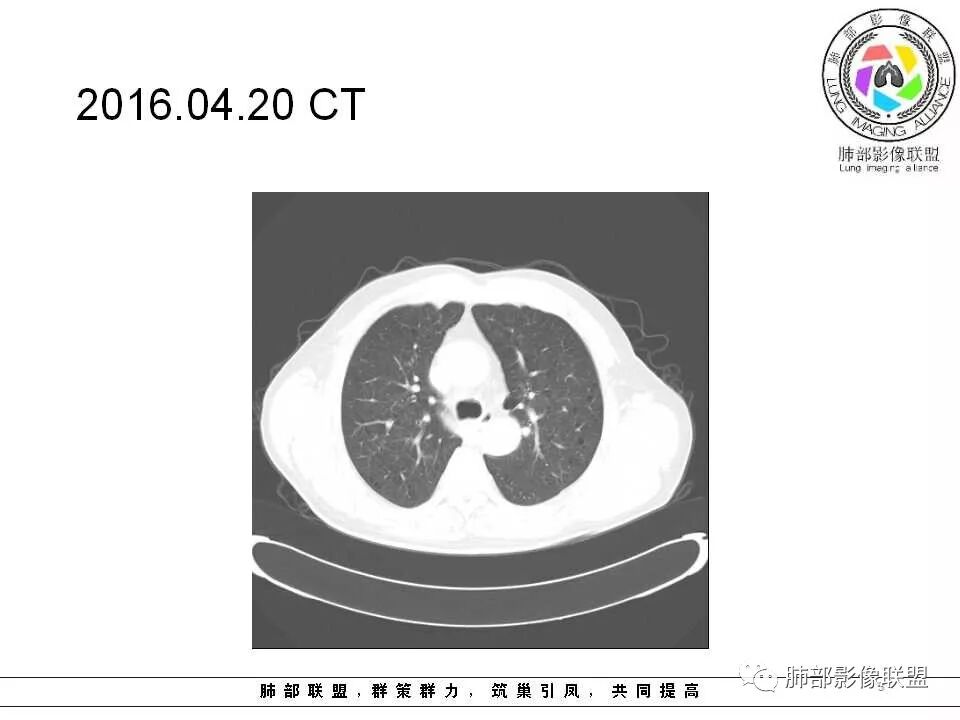

老年男性,肺气肿基础。约一年时间出现左肺上叶舌段支气管近端结节影,远端斑片样阴影,边缘模糊。考虑近端恶性占位,远端有阻塞性炎症。

老年男性,两肺可见小叶中央型肺气肿,提示应该有抽烟史。2016年片,右肺门支气管稍模糊,考虑慢性感染,纵膈淋巴结稍大。但2017年左肺上叶新发占位,堵塞支气管,引起局部肺不张伴感染,且纵膈淋巴结较2016年变大,患者同时伴有咯血,考虑恶性。鳞癌?类癌?小细胞?

肺气肿背景,2016年左肺上叶上舌段见微结节,2017年5月左肺结节增大,密度均匀,边缘光滑锐利,与邻近血管关系密切,血管贴壁走行,外侧见尖状突起,下舌段片状影,沿着支气管走行,内有粘液栓,考虑鳞癌,鉴别小细胞肺癌。

肺气肿背景,2016年左肺上叶上舌段见微结节,一年后左肺结节增大,密度均匀,边缘光滑、膨隆,似见小分叶,下舌段片状影,沿着支气管走行,内,老年患者,咯血1月。考虑恶性病变并阻塞性肺炎,鳞癌?注意鉴别结核。

左肺上叶舌段支气管管壁略增厚 间隔一年 管壁增厚明显 向腔外突出形成结节 管腔闭塞 远端片状及斑片影 纵隔淋巴结增大 肺气肿背景 考虑鳞癌伴阻塞性炎症可能

老年男性,咯血1月,肺气肿背景,16年左肺上叶舌段结节,左肺门疑似淋巴结肿大,呈结节感。17年左肺上叶舌段见沿支气管走行分布结节 远端阻塞性肺炎,左肺门淋巴结肿大明显,首先考虑恶性病变,鳞癌?类癌?

前次片2016年4月20相应位置就有小点状病灶,2017-5-15呈结节影改变,边界膨隆,远端阻塞炎性改变,考虑肺癌,鉴别炎性结节!

老年男性,肺气肿背景,左肺上叶舌段一年前小结节后长大,实性,与邻近气管关系密切,远端有少许小片状炎症类小结节状,左肺门淋巴结肿大,首先考虑恶性,鳞癌可能性大,代排小细胞癌。病灶下方斑片状影,考虑炎症。

老年男性,肺气肿背景,对比前片,左肺上叶舌段结节较前进展,周围有斑片状条状密度增高影,左肺门淋巴结肿大,有咯血史抗炎后效果不佳,目测增强强化不好判断,考虑肺癌并阻塞性肺炎可能,鉴别炎症性肺癌,真菌类肺炎,肺脓肿,肺结核,建议完善肿瘤标志物,结核相关检查,病原体检查。

老年男性,咯血一个月,有慢支病史。左肺上叶舌段可见一类圆形结节影,边缘光滑,远端有片条状影,一年前胸ct基本正常。感觉还是考虑肺癌合并阻塞性炎症。鳞癌还是小细胞?